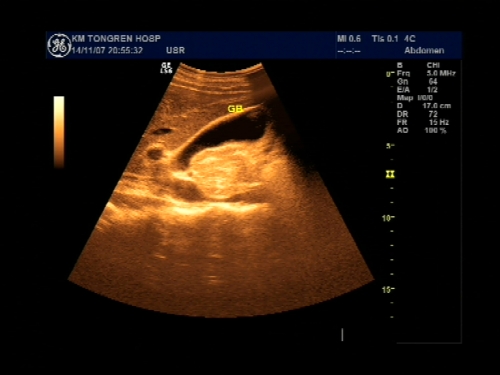

超声声像图能显示肝脏切面形态、大小、肝内实质结构、管道系统及肝周邻,并能根据肝内管道系统区分肝脏各叶、各段,对病变进行定位诊断。彩色多普勒超声能显示肝脏的血流,并能对肝脏的血流动力学参数进行测定,不仅能诊断肝脏的血管病变,还能了解正常肝脏及病变肝脏的血供及回流状态,目前已成为临床诊断肝脏疾病的常规检查方法。

右肋间斜断扫查

肝缘下斜断扫查